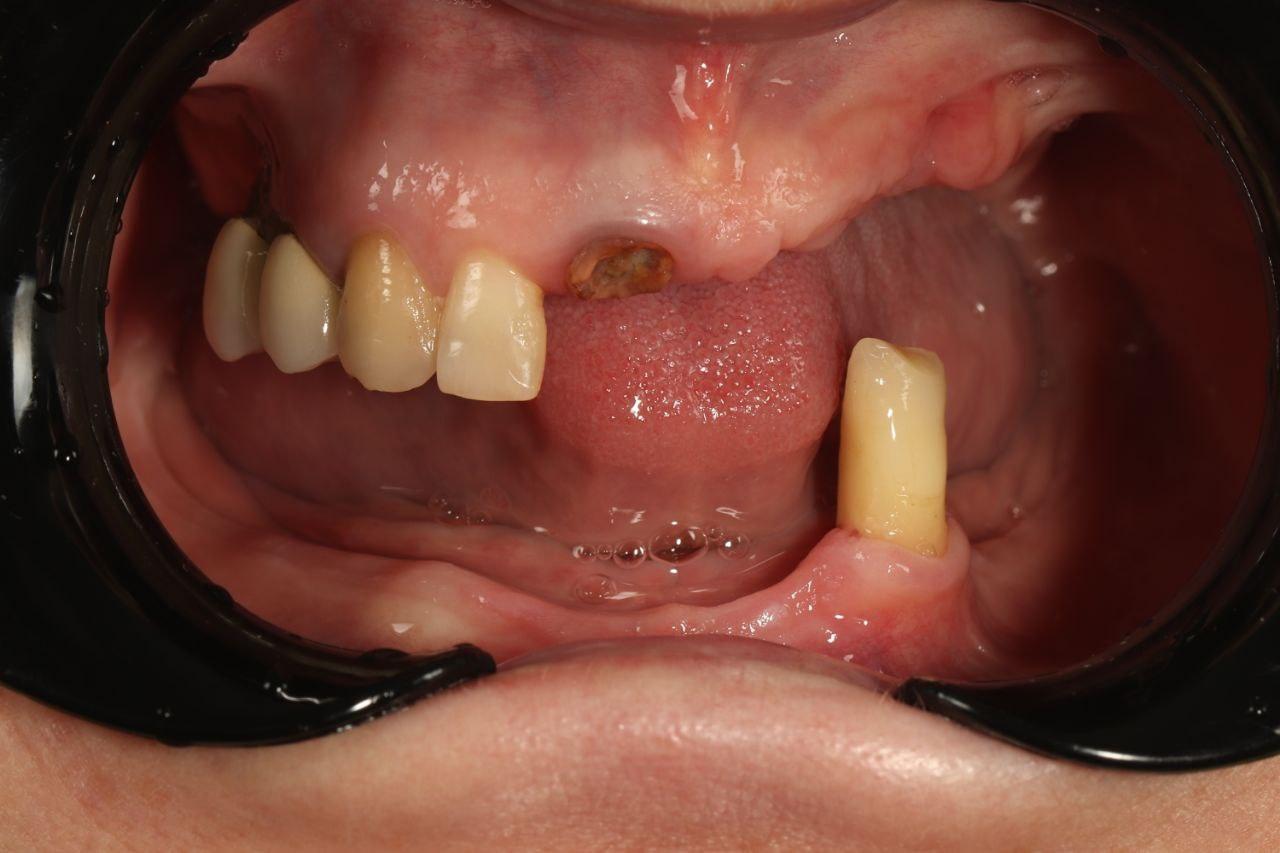

Имплантация

Протезирование